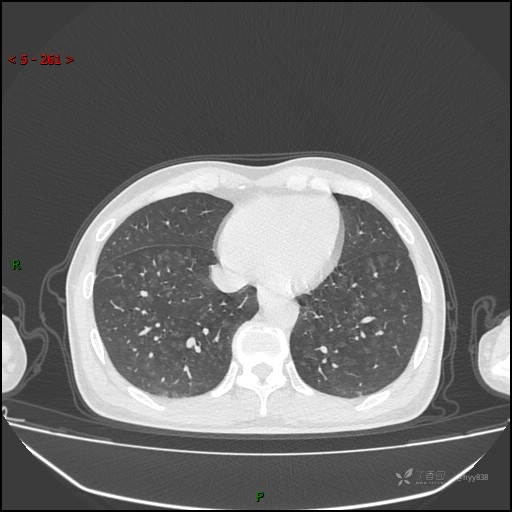

性别:男

年龄:55岁

简要病史:渐进性呼吸困难。

实验室检查:血象正常。

临床诊断:呼吸困难待查

胸部CT平扫

电焊工尘肺 (2)